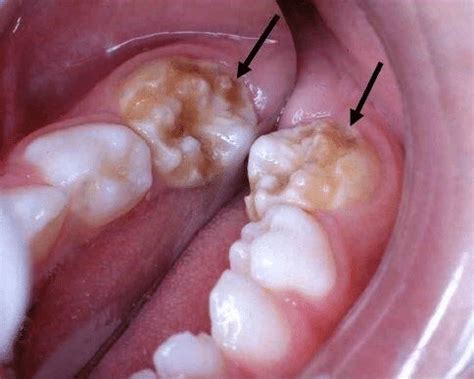

The appearance of enamel hypoplasia can vary. You might see small pits or grooves on the surface of the teeth, or the teeth might have a rough, uneven texture. In more severe cases, there might be large areas of missing enamel, exposing the underlying dentin, which is softer and more prone to decay. Sometimes, the teeth can also appear discolored, with white, yellow, or brown spots. The location and severity of the defects depend on when the disruption occurred during tooth development and what caused it. For example, if the disruption happened early on, it might affect a larger portion of the tooth. Identifying enamel hypoplasia early is crucial because it can lead to several dental issues down the line. Because the enamel is thinner or weaker, teeth are more susceptible to cavities. They can also be more sensitive to temperature changes, making it uncomfortable to eat hot or cold foods. Additionally, the altered appearance of the teeth can affect a person’s self-esteem. Knowing what to look for and seeking timely dental care can help manage these issues and protect your smile. Remember, a healthy enamel is your best defense against tooth decay, so taking care of it is super important!